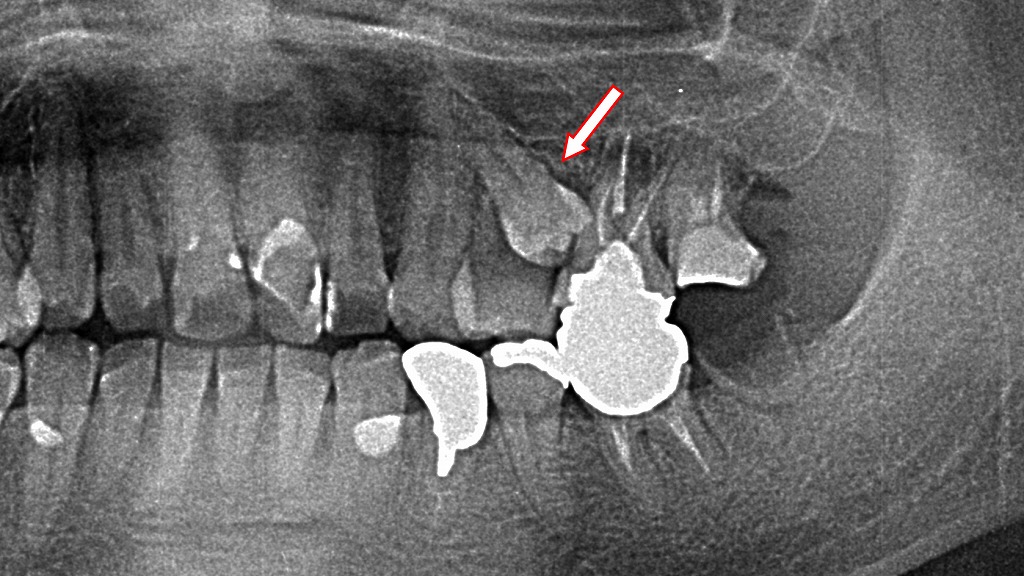

小臼歯が埋伏歯となったレントゲン画像

このレントゲン画像(パノラマX線)は、上下の歯列全体を写したものです。

赤い矢印で示された部位には埋伏歯(まいふくし)が確認されます。以下にそれぞれ解説します👇

🦷 上顎の小臼歯の埋伏歯

上顎の小臼歯(第二小臼歯)が骨内に完全に埋まっており、生えてきていません。

このような小臼歯の埋伏はまれですが、永久歯の萌出方向の異常や乳歯の早期脱落などが原因となることがあります。